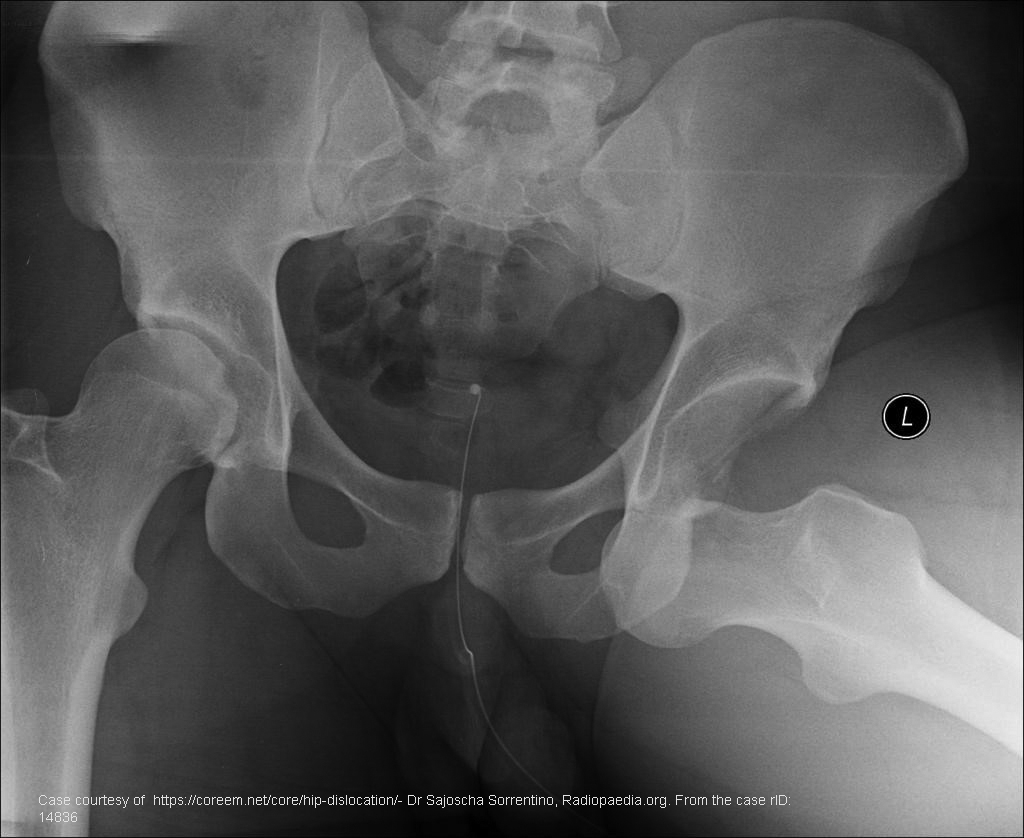

Where is the femoral head in a posterior dislocation?

Posterior and superior to the acetabulum.

What is the most common type of hip dislocation?

Posterior dislocation.

How does the limb typically present in a posterior dislocation?

Flexed, adducted, and internally rotated hip with a shortened leg.

What mechanism often causes posterior hip dislocation?

Force applied to a flexed and adducted hip (e.g., dashboard injury).

What key imaging feature distinguishes posterior hip dislocation?

Internally rotated and shortened limb with femoral head displaced superior and posterior to the acetabulum.